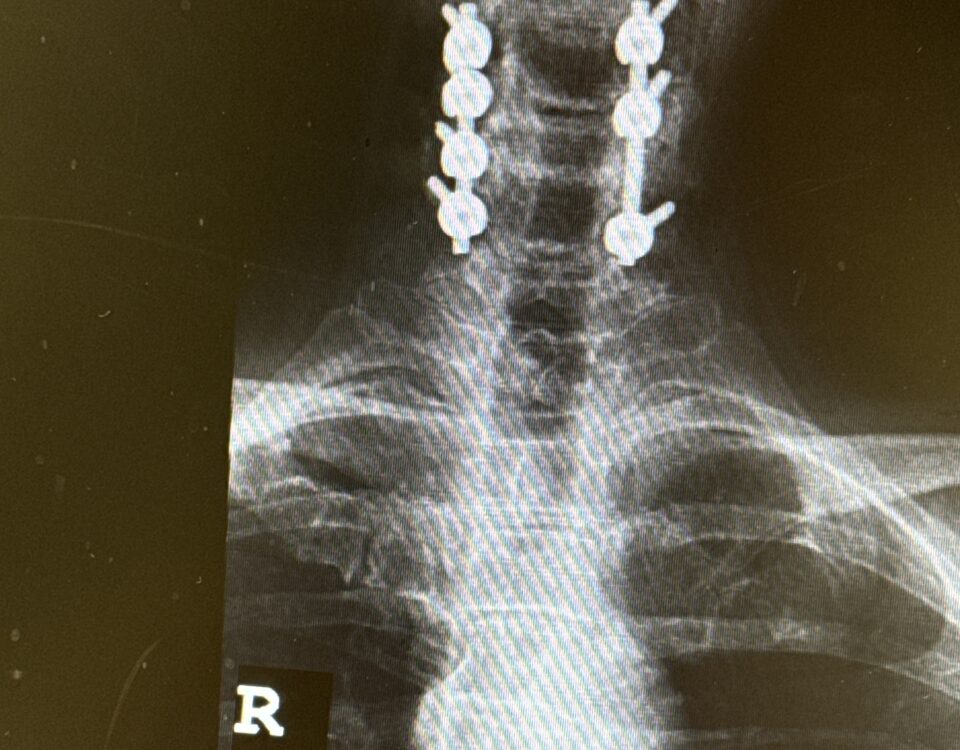

Patients may require an occipital-cervical fusion for both cranio-cervical and atlanto-axial instability, depending on the anatomy. Patients who have long segment posterior cervical fusions can sometimes […]